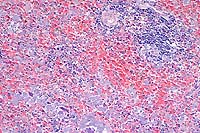

- Case 3-1. Haired skin. Diffusely (here, Left, 20x

obj) replacing normal dermal elements, there is an cellular infiltrate

composed of high numbers of neutrophils, fewer epithelioid macrophages,

lymphocytes, and plasma cells with rare foreign body type giant

cells (lower left). There are rare 15-20u diameter oval yeast

bodies with a basophilic central zone surrounded by a clear eccentric

halo (upper right). Gomori Methenamine Silver (Right, GMS 40x

obj) staining highlights yeast bodies which are occasionally

forming broad based buds.